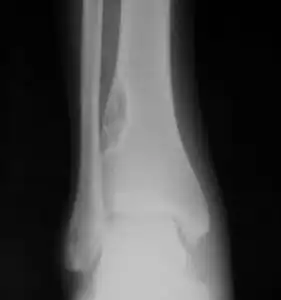

X-ray of nonossifying fibroma of distal tibia.

Diagnosis is by X-ray or MRI, usually when investigating a person for something else.[3] Medical imaging typically shows a well marginated radiolucent lesion, with a distinct multilocular appearance, sometimes looking like bubbles.[3] It is usually around 1-2cm in size, but be as large as 7cm.[4] They consist of foci consist of collagen rich connective tissue, fibroblasts, histiocytes and osteoclasts.[3] Usually no treatment is required.[4] Surgical curettage and bone grafting may be required if it is large.[4]

It is usually iagnosed by x-ray or MRI, when investigating another problem.[1] The tumor presents as a well defined radiolucent lesion, with a distinct multilocular appearance, sometimes looking like a "soap bubble".[2] If small and no symptoms, then biopsy is not needed.[1]